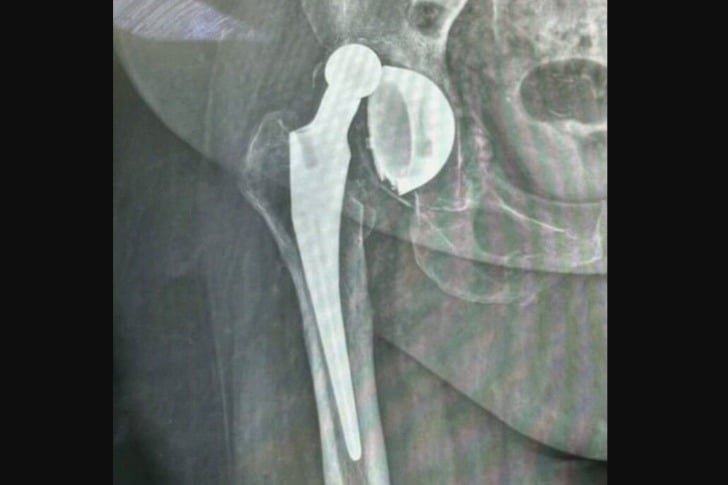

#21 Cette chose sphérique est censée être À L’INTÉRIEUR de la cavité de la hanche.

Cela peut arriver après une arthroplastie de la hanche si vous ne suivez pas les instructions concernant l’élévation et l’absence d’hyperextension de l’articulation pendant une certaine période. Cela peut également se produire à la suite d’une chute plus tard.